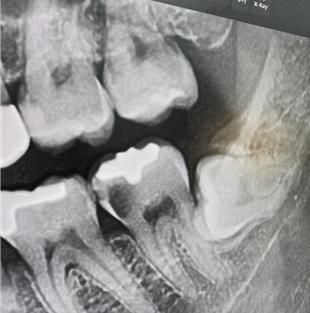

치아 x-ray 한번 봐주시면 감사하겠습니다.

사랑니 옆 치아 입니다.

사진으로 봤을 경우 사랑니 앞의 치아는 충치가 많이 진행되어 있는것으로 보입니다. 충치가 치아의 뿌리까지 진행이 되었다면 발치를 해야 하는 상황이 발생할수 있습니다.

충치가 크기 때문에 빠르게 치료를 하는것이 좋을것으로 생각됩니다

엑스레이 상으로만 봐도 충치가 상당히 많이 진행된거 같습니다. 신경치료를 해도 예후가 많이 안좋을수도 있습니다.

사랑니 바로앞 치아가 많이 썩어 있으며 사랑니와 맞닿는 부위 잇몸뼈도 내려간 상태 입니다. 이런 경우 어금니 예후가 별로 좋지 않습니다. 일단 신경치료 크라운 시도 해 보고 안되면 뽑는 것도 생각해야 합니다.